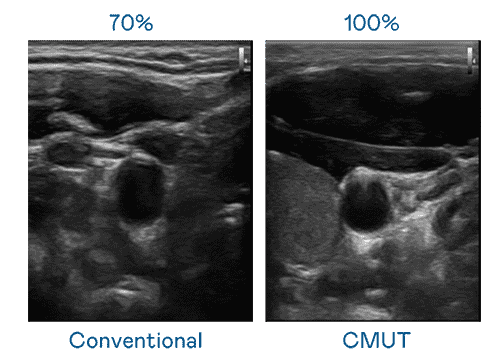

CMUT 技术是一种用电容式微机电元件来产生超音波讯号的技术。。与传统 PZT 压电式技术相比,,,,CMUT 频宽增加 30%,,,,更宽频的超音波讯号让影像解析度大幅提升,,,,是实现高影像品质医疗超音波扫描、、促进精准医疗发展的关键技术。。

超音波影像的解析度高低,,,首先取决于探头能发出的讯号频宽。。。。z6尊龙 CMUT 可提供高清晰的超音波讯号,,,,提供高频宽、、高灵敏度、、、影像纹理细节更高的超音波影像,,,,协助医护人员缩短影像判读时间及利用精准的医疗影像进行诊断。。